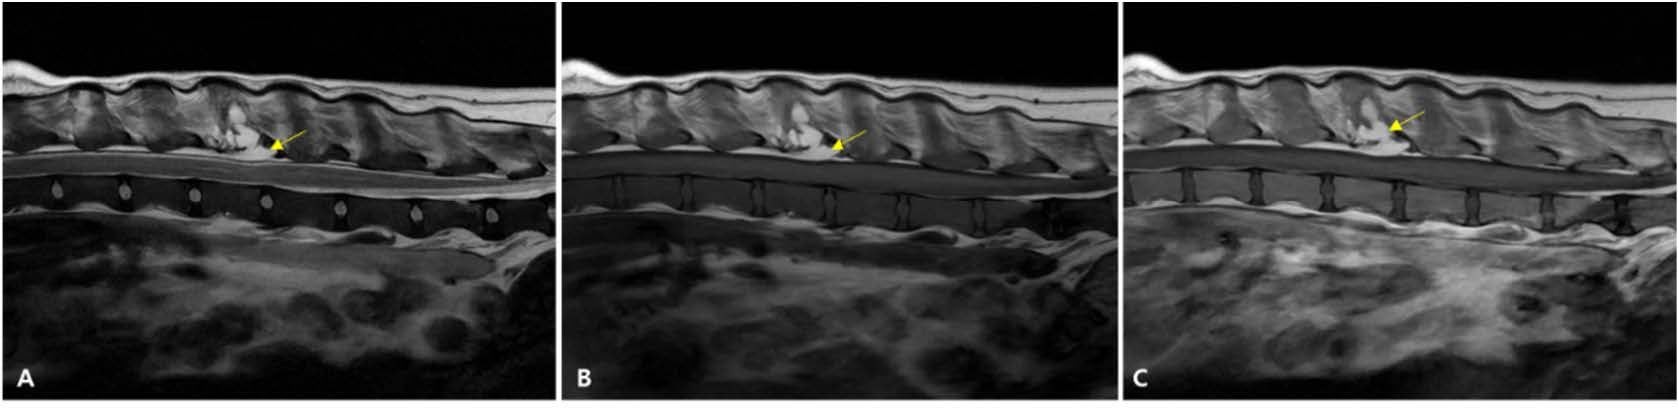

第394天,进行了MRI,以调查新出现的尿潴留。未发现中枢神经系统病变。L3椎体病变在T1加权和T2加权图像上均显示出脂肪信号,并且体积缩小,对脊髓的压迫极小(下图)。

↑ 第395天L3-L4椎体水平的MRI。(A) T2加权图像(T2WI),(B) T1加权图像(T1WI),(C) 增强T1加权图像。经过治疗的L3肿块(A-C中的箭头)在T2WI和T1WI上均显示出高信号强度,符合脂肪特征,并且体积缩小。脊髓压迫几乎完全缓解。